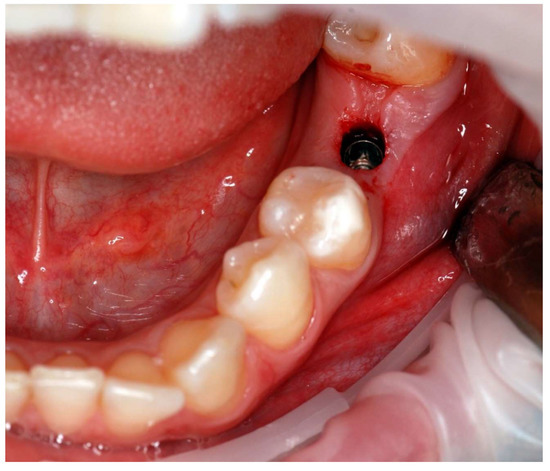

The implant placement procedure was performed by a team of two dental surgeons with over 20 years of clinical experience. The procedures were performed under local infiltration anesthesia and block anesthesia using 4% articaine as anesthetic. The implant bed preparation was performed using a flapless approach. Each of the rotary instruments, including the punch, was calibrated and detected by the navigation system before being introduced into the surgical field, as shown in Figure 2.The drilling sequence for the Camlog implant system was used for the surgery, while the implant placement protocol was followed. The implants, as well as the surgical instruments, were calibrated and inserted under navigation guidance. The procedure was completed by securing the implant body with a locking screw, there was no need to suture a wound-Figure 3.

Figure 3. Tissue status immediately after implantation in the flapless technique—no need for wound suturing.